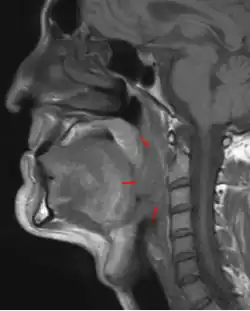

| 3D medical illustration showing the cancer formation in the tissues of the oropharynx | |